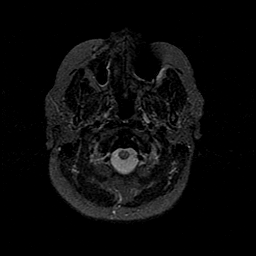

MR Study #1 -- Slice #5

[Home][Help][Clinical][Tour 1][Tour 2][Tour 3] Slice 5